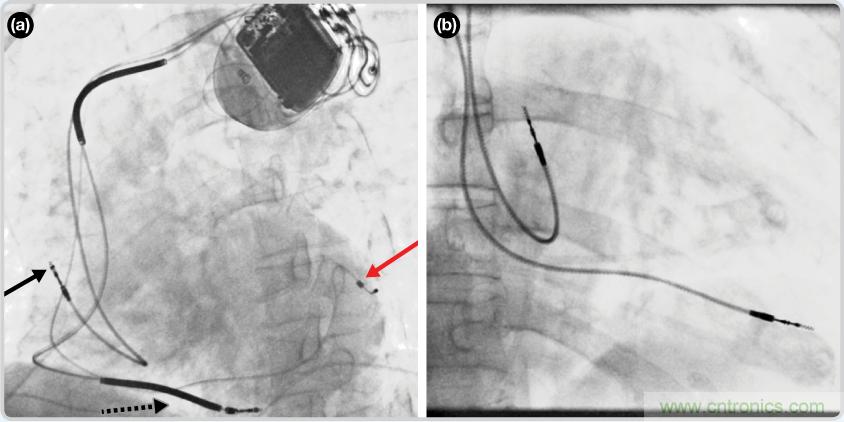

CRT器件在圖4(a)中的透視圖像中可以看見。醫(yī)師就是利用這種影像來放置導聯(lián)線的。對于非專業(yè)人士來說,這種影像是很難解讀的??梢钥吹叫呐K淡淡的輪廓——這是搏動中的心臟的靜態(tài)視圖。起搏器位于右心房上,心臟頂點指向右下方。在這個典型的導聯(lián)線放置實例中,黑色箭頭指向右心房導聯(lián)線。虛線黑色箭頭指向右心室導聯(lián)線。紅色箭頭標示的導聯(lián)線只能看到一部分,這是左心室導聯(lián)線(紅箭頭指向電極尖端)。圖4(b)展示的是雙腔起搏器的典型導聯(lián)線放置透視圖像。右心房導聯(lián)線指向上方,置于右心房中。右心室導聯(lián)線則位于右心室頂部。

圖4. 起搏器導聯(lián)線放置的透視圖像3 (a). 單腔起搏器;(b).雙腔起搏器